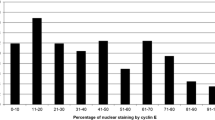

Patient and tumor characteristics according to cyclin D1 status are shown in Table 1. Median cyclin D1 expression was 61.7, 68.7% in ER-positive tumors and 34.3% in ER-negative cases. The association between ER content (percent nuclear staining) and high cyclin D1 was highly significant (Table 2). Cyclin D1 expression was below 1% in 1 of 242 ER-positive cases (0.4%) and in 6 of 115 ER-negative cases (6%). The distributions of cyclin D1 values were different in ER-positive and ER-negative tumors. Although overlapping, cyclin D1 peaked at 80% in ER-positive and less than 5% in ER-negative tumors (Fig. 2).